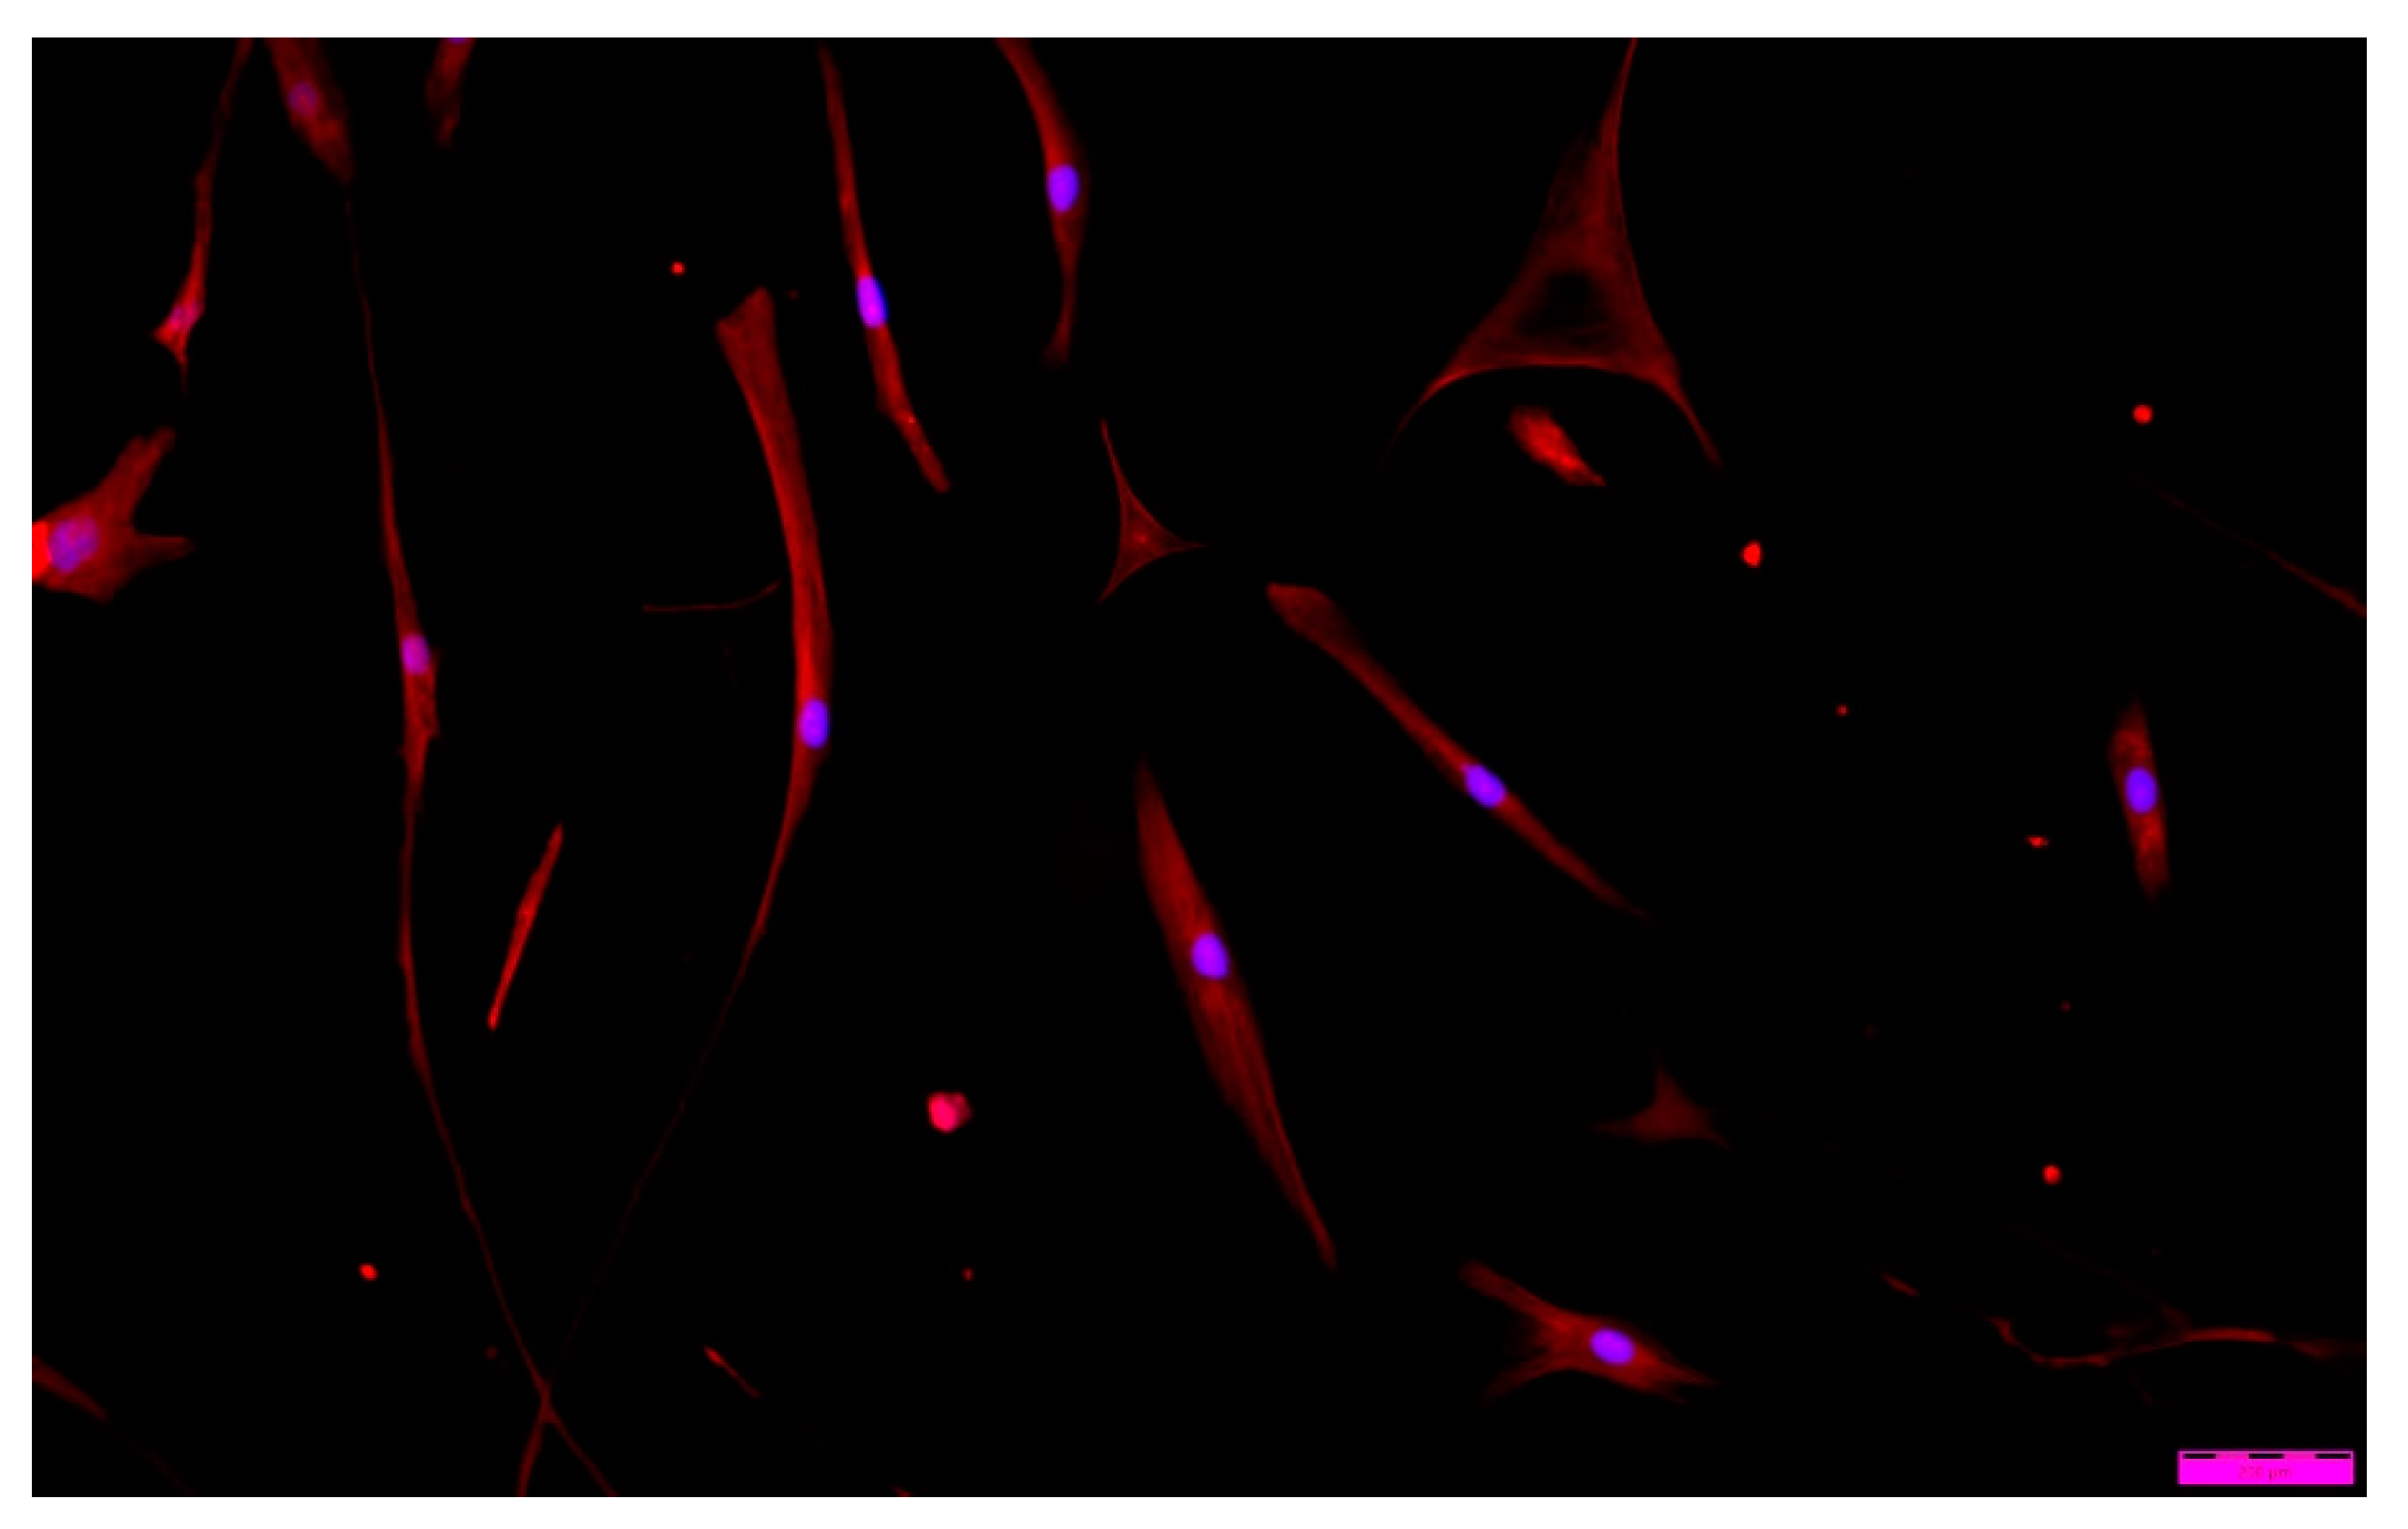

When analyzing ‘cell’ morphology using fluorescence microscopy, it was observed that cells grown in the presence of ALG-PFC and (ALG-PFC)net membranes show the correct morphological picture (Figure 12 and Figure 13). After six days of the culture, we observed numerous cells on the surface of glass coverslips coated with ALG-PFC and (ALG-PFC)net. In addition, the spindle-shaped cells of fibroblastoid features were present on both types of surfaces.

Figure 13. Fluorescence microscopy image of human fibroblast cells cultured in the presence of a cross-linked alginate–perfluorooctyl coating ((ALG-PFC)net) after a 6-day culture.